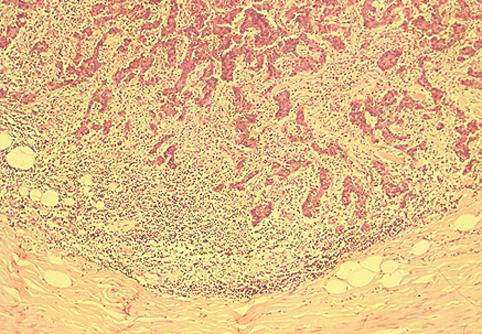

部位(按器官分)大肠/盲肠

检查方法病理切片(微观)

肿瘤的肉眼分类0型(表在型)/其他

肿瘤最大直径20~24

肿瘤的深度sm